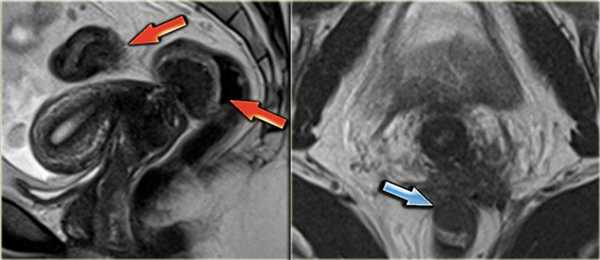

На Т1 и Т2 взвешенных томограммах у пациентки с эндометриозом визуализируются «целующиеся» яичники, расположенные вплотную друг к другу из-за множественных спаек. Также видны небольшая геморрагическая киста в левом яичнике и поверхностная геморрагическая бляшка, дающие гиперинтенсивный сигнал (красные стрелки)

Эндометриоз, осложненный гидронефрозом. На Т2 взвешенных томограммах определяется дилятация левого мочеточника в его дистальных отделах, обусловленная выраженной глубокой эндометриоидной инфильтрацией с поражением левой крестцово-маточной связки и распространением на сигмовидную кишку